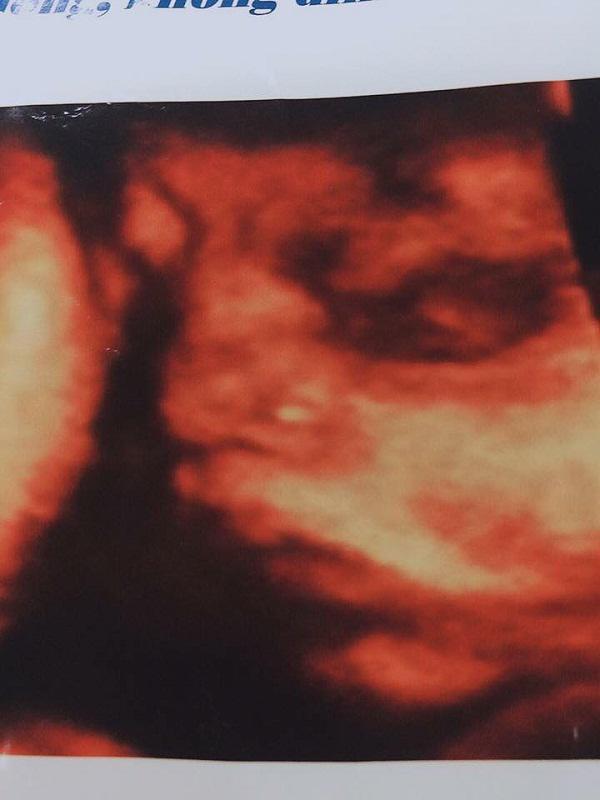

Hình ảnh con anh Lương khi siêu âm trước khi mất.

Kể từ đó anh từng ngày mong con chào đời và hết lòng chăm sóc vợ bầu. “Tôi và vợ không hề có mâu thuẫn gì, từ lúc mang thai vợ tôi lần nào đi siêu âm cũng gửi hình ảnh con về cho tôi xem.